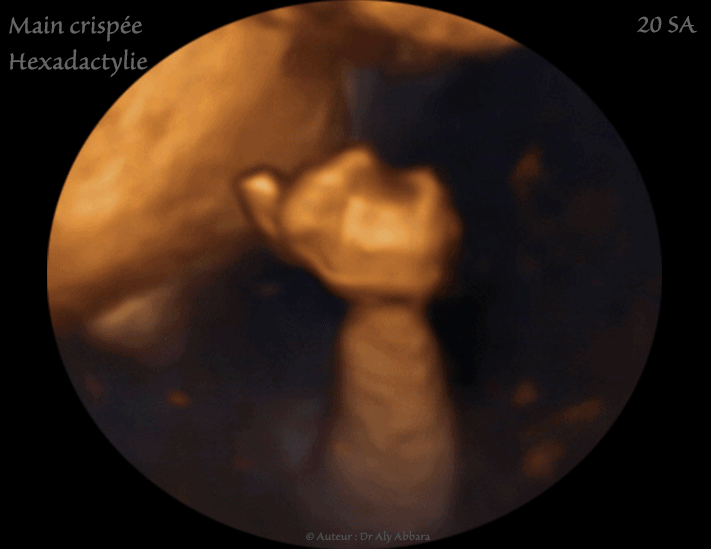

Images échographiques en 2D et en 3D montrant l'aspect ultra-sonre d'une main crispée avec chevauchement des doigts des mains : l'index recouvre le majeur et l'auriculaire recouvre l'annulaire.

Ce Signe est retrouvé dans 50 % des cas de trisomie 18.

L'hexadactylie est la deuxième malformation de la main identifiable sur ces images échographiques.